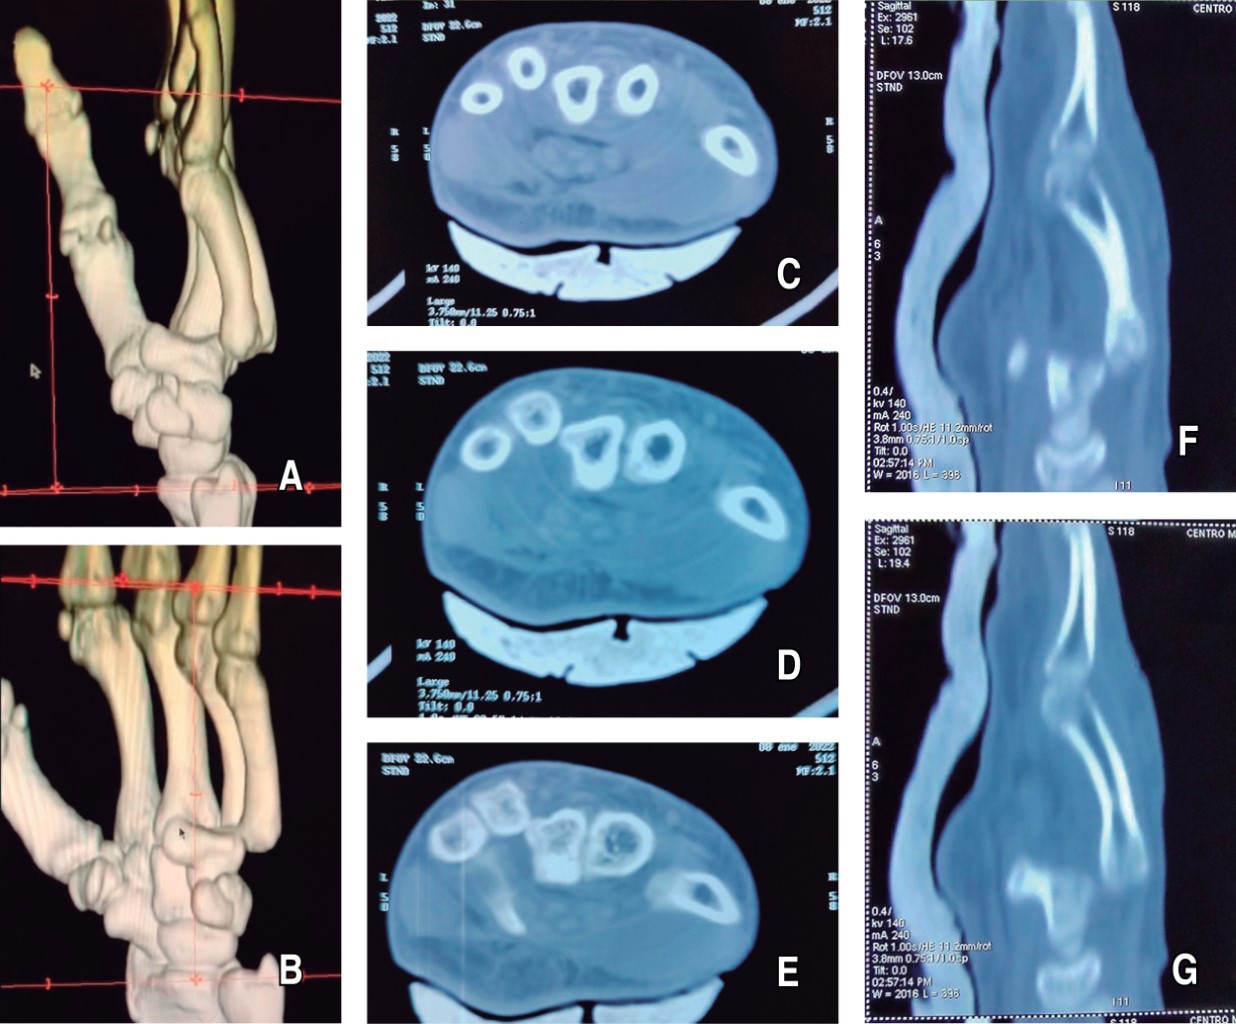

Paciente acude a la consulta externa ocho meses después del procedimiento para seguimiento, describe extremidad superior izquierda indolora, con capacidad para las actividades cotidianas sin compromiso, reintegración recreativa deportiva al kickboxing sin compromiso. A la inspección con presencia de cicatriz longitudinal sin contractura dérmica o articular. A la exploración dirigida, con capacidad para la flexión y extensión de la muñeca, rotación de la muñeca, abducción y aducción de la mano, capacidad de puño y oposición de los dedos de mano, comparados con la mano contralateral, por lo que se considera arcos de movilidad completos, sin secuelas visibles a la movilización. Sin dolor a la palpación profunda de la articulación carpometacarpiana del cuarto y quinto dedo, llenado capilar inmediato, buen color de piel, sensibilidad presente, por lo que se considera mano izquierda sin compromiso (Figura 5).

Se realiza tomografía simple en la que se observa congruencia articular de la base del cuarto y quinto metacarpiano, alineación y congruencia de los huesos del carpo y de los metacarpianos de la mano izquierda (Figura 6).

Figura 5

Figura 6